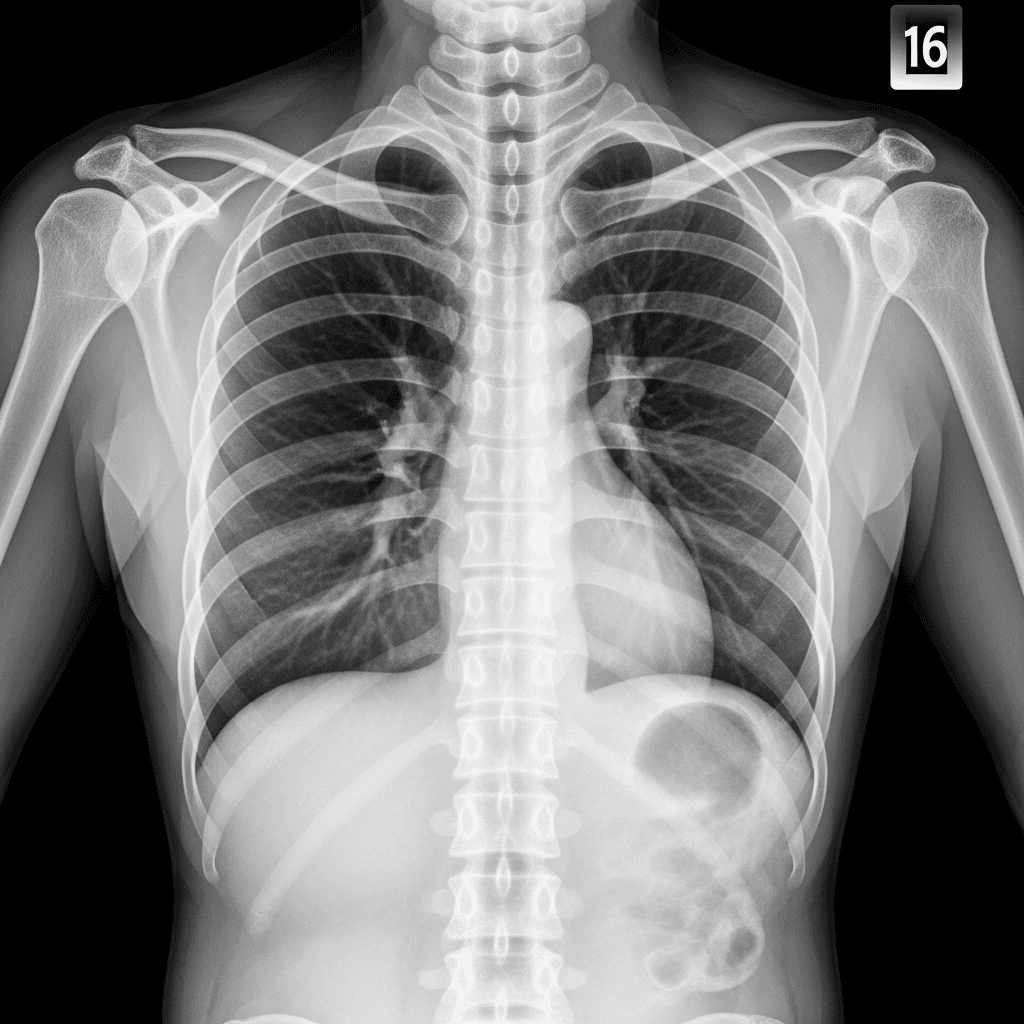

Symptome eines katamenialen Pneumothorax

Eine ernste Komplikation dieser Erkrankung ist ein Lungenkollaps, der synchron zur Menstruation auftritt. Dies wird medizinisch als katamenialer Pneumothorax bezeichnet.

Hauptsymptome sind plötzliche stechende Brustschmerzen, Schulterschmerzen und Kurzatmigkeit. Sofortige Notfallversorgung ist erforderlich, wenn Sie plötzliche Atembeschwerden verspüren.

Diagnose- und Behandlungswege

Ärzte diagnostizieren diesen Zustand oft mittels CT-Scans oder videoassistierter Thorakoskopie (VATS). Es ist eine komplexe Erkrankung, aber mit dem richtigen Team beherrschbar.